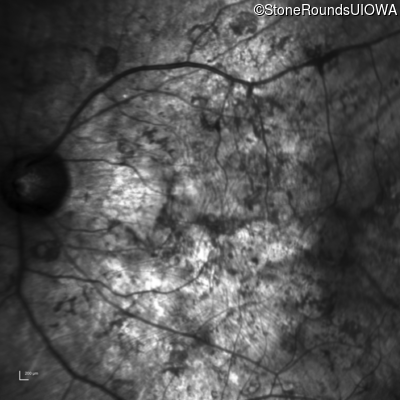

Infrared Fundus Photograph - Left - Hand Motion 1' sc

Exemplar